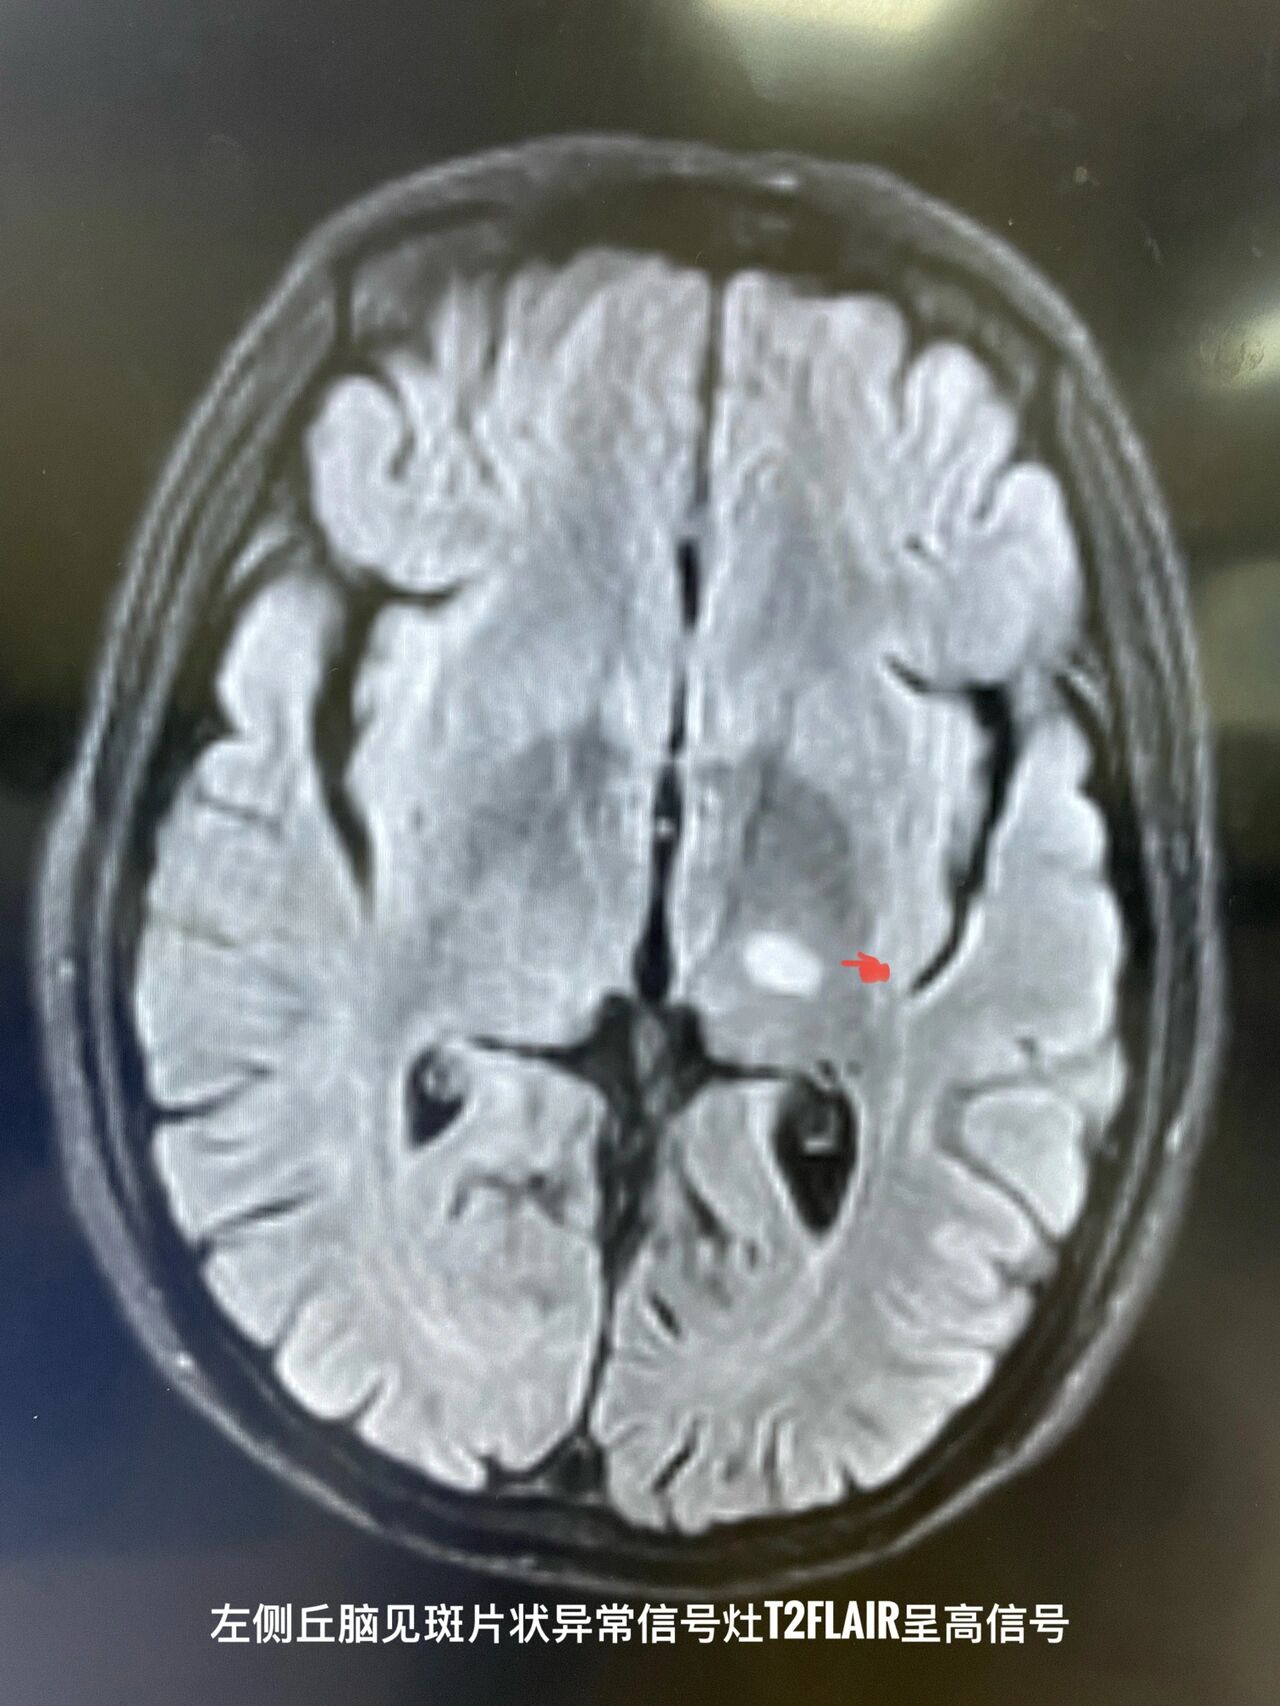

脑干急性梗死